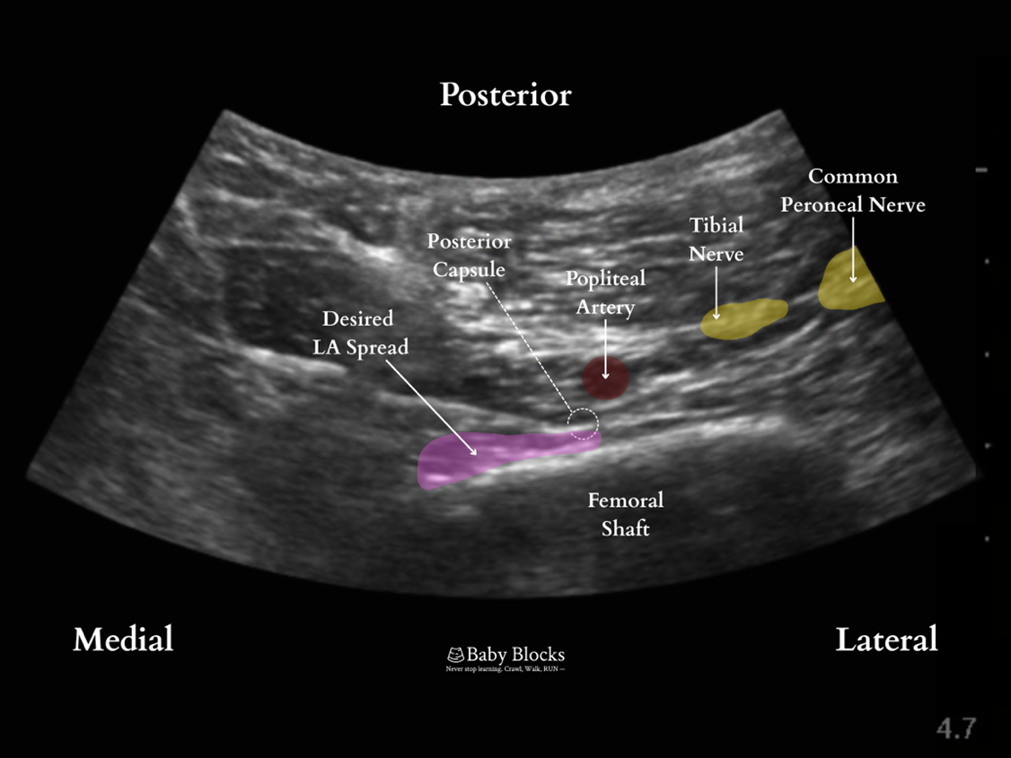

Interspace between the popliteal artery and the posterior capsule of the knee

The iPACK is essentially a field block of the terminal genicular branches of the posterior knee. Distal injection at the level of the femoral condyles results in more anterolateral spread while proximal injection at the level of the femoral shaft 1 cm, proximal to the base of the patella, results in more consistent spread anteromedially. Often used in conjunction with adductor canal block and genicular blocks to provide motor-sparing analgesia of the posteromedial knee joint.

Relevant Anatomy: femoral condyles, femur, muscles, popliteal artery and vein

Lateral border: femur anterior to the popliteal artery

Anterior border: posterior aspect of the femur

Medial border: medial edge of the femur

· Scanning is performed along the femur to find the posterior view of the femoral condyles.

· The probe is translated proximally until the condyles disappear from view and the femur is seen as a flat hyperechoic line.

· The needle is advanced in-plane to make contact with the femur proximal to the knee joint on the medial aspect of the popliteal artery. Local anesthetic is deposited along the femur taking care not to deposit local anesthetic lateral to the popliteal artery to avoid sciatic nerve involvement and a foot drop.

At the level of the femoral shaft. Popliteal artery is seen posterior to the femur, with the needle advancing from medial to lateral to make contact with the posterior femur just anterior to the artery.

Post-injection. Local anesthetic is infiltrated along the femur. Injection is made while withdrawing needle with spread visualized anteromedial to the artery